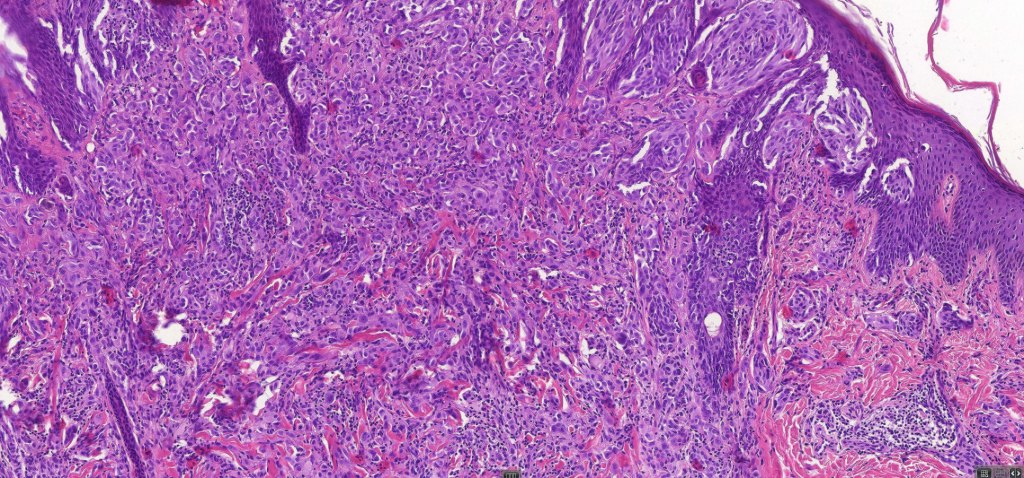

The term atypical Spitz nevus/tumor was introduced as a means of separating out those lesions which show features of a Spitz nevus with some but not all of those seen in melanoma. It implies diagnostic uncertainty. While the reason for its introduction is laudable, the term has been inappropriately abused by some for any Spitz nevus showing the slightest deviation from the classical features. The term has turned into a dumping ground particularly for the inexperienced. Although not completely true, the statement by the late Bernie Ackerman that “atypical Spitz nevus comprises an admixture of Spitz nevi and melanoma” with nothing else has merit. The term should not be applied lightly as it is certainly associated with risk of sentinel node spread & sometimes beyond. I have never been keen on the entity. While I agree that not all cases are readily characterized as benign or malignant, I do believe that the over whelming majority of cases can and should be. I used to tell the residents and fellows the following potted history. A patient was noticed by his/her partner to have an odd pigmented lesion on the back. The patient went to the general practitioner who agree that it was odd and arranged for a dermatology referral. The dermatologist also thought that it was odd and excised it. The pathologist agreed that it was odd but didn’t know if it was benign or malignant. The patient and his/her partner wondered why they has bothered worring about it in the first place!

Expansile dermal nests (these are particularly worrysome as they are common and important feature of melanoma)

Imapired maturation

Pushing deep border (in Spitz nevus, the lower border typically infiltrates the adjacent dermis)

Excessive mitotic activity,

Deep mitoses,

It is stressed that the presence of only some of these features are consistent with the diagnosis of atypical Spitz nevus. If many are present, it is much more lkely that the lesion is a melanoma.